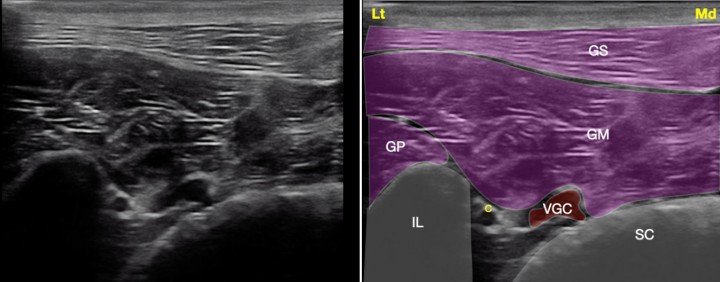

<p>Imagen ecográfica del plexo sacro a nivel de la escotadura ciática mayor. Músculo glúteo superficial (GS), músculo glúteo medio (GM), músculo glúteo profundo (GP), ilion (IL), sacro (SC), nervio ciático (C), vasos glúteos caudales (VGC). Lt: Lateral, Md: Medial.</p>

Figura 4

Imagen ecográfica del plexo sacro a nivel de la escotadura ciática mayor. Músculo glúteo superficial (GS), músculo glúteo medio (GM), músculo glúteo profundo (GP), ilion (IL), sacro (SC), nervio ciático (C), vasos glúteos caudales (VGC). Lt: Lateral, Md: Medial.

Bloqueo del nervio ciático con abordaje parasacral

Se localiza la cresta ilíaca y la tuberosidad isquiática trazando una línea recta que las una. Esta línea se divide en tres tercios, y en la confluencia del primer y segundo tercio se coloca el transductor de forma perpendicular a la piel, cortando el ilion transversalmente. Se debe utilizar una sonda de alta frecuencia (9-15 MHz) modificando la frecuencia en función del tamaño del paciente. En este punto se encuentra la escotadura ciática mayor, y de ella emerge el plexo sacro que comprende los nervios ciático, glúteo craneal y caudal y el femoral cutáneo caudal. A este nivel, el plexo sacro en su corte transversal se observa como un grupo de estructuras hipoecogénicas, rodeadas de un halo hiperecogénico pegadas al ilion junto a la arteria y la vena glútea caudal[ Portela DA, Verdier N, Otero PE: Regional anesthetic techniques for the pelvic limb and abdominal wall in small animals: A review of the literature and technique description. Vet J 2018; 238: 27-40. [PubMed] , Shilo Y, Pascoe PJ, Cissell D, et al E: Ultrasound-guided nerve blocks of the pelvic limb in dogs. Vet Anaesth Analg 2010; 37: 460-470. [PubMed] , Marolf V, Rohrbach H, Bolen G, Van Wijnsberghe AS, Sandersen C: Sciatic nerve block in dogs: description and evaluation of a modified ultrasound-guide parasacral approach. Vet Anaesth Analg 2019; 46: 106-115. [PubMed] ] (Fig. 9). La aguja se introduce en plano desde dorsomedial a ventrolateral. En caso de duda se puede neuroestimular el plexo, buscando la contracción del gastrocnemio o la dorsiflexión/extensión del tarso. En este punto se deposita el AL en un volumen de 0,05-0,1 ml/kg de AL. Se recomienda el empleo de bupivacaína 0,5% o ropivacaína 0,5% con 0,5-1 µg/ml de dexmedetomidina.